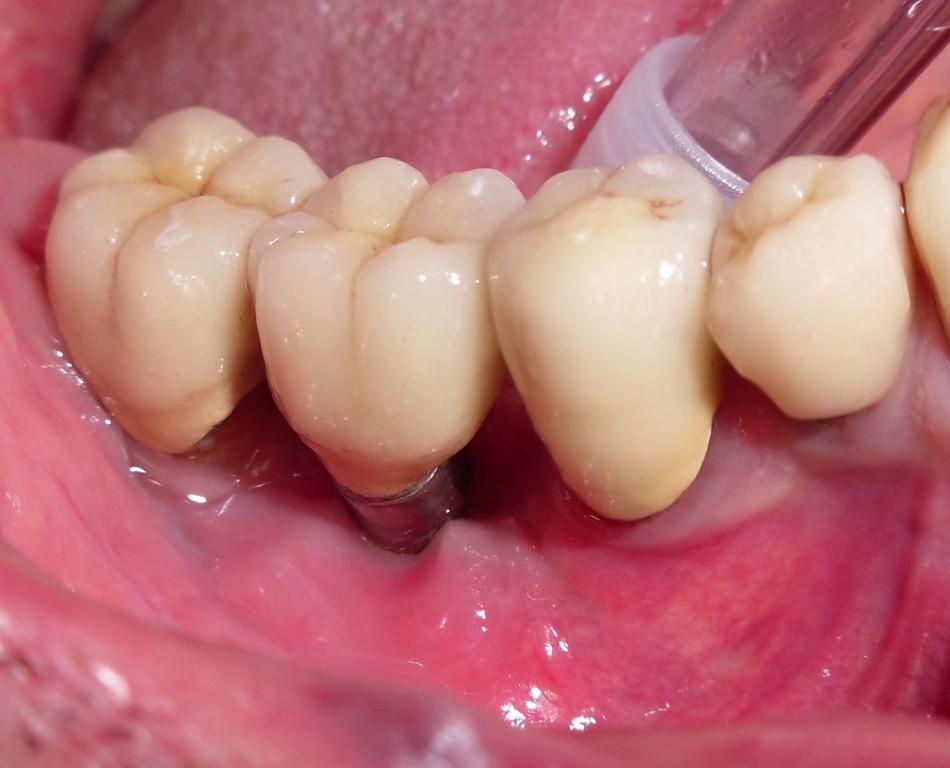

Viene presentato un caso clinico di una periimplantite affrontato mediante terapia ossea resettiva.

La compliance del paziente prima della chirurgia e' molto bassa e sara' opportunamente corretta prima della fase chirurgica.

Il paziente presenta limitazioni della manualita' derivanti da un pregresso infarto cerebrale.